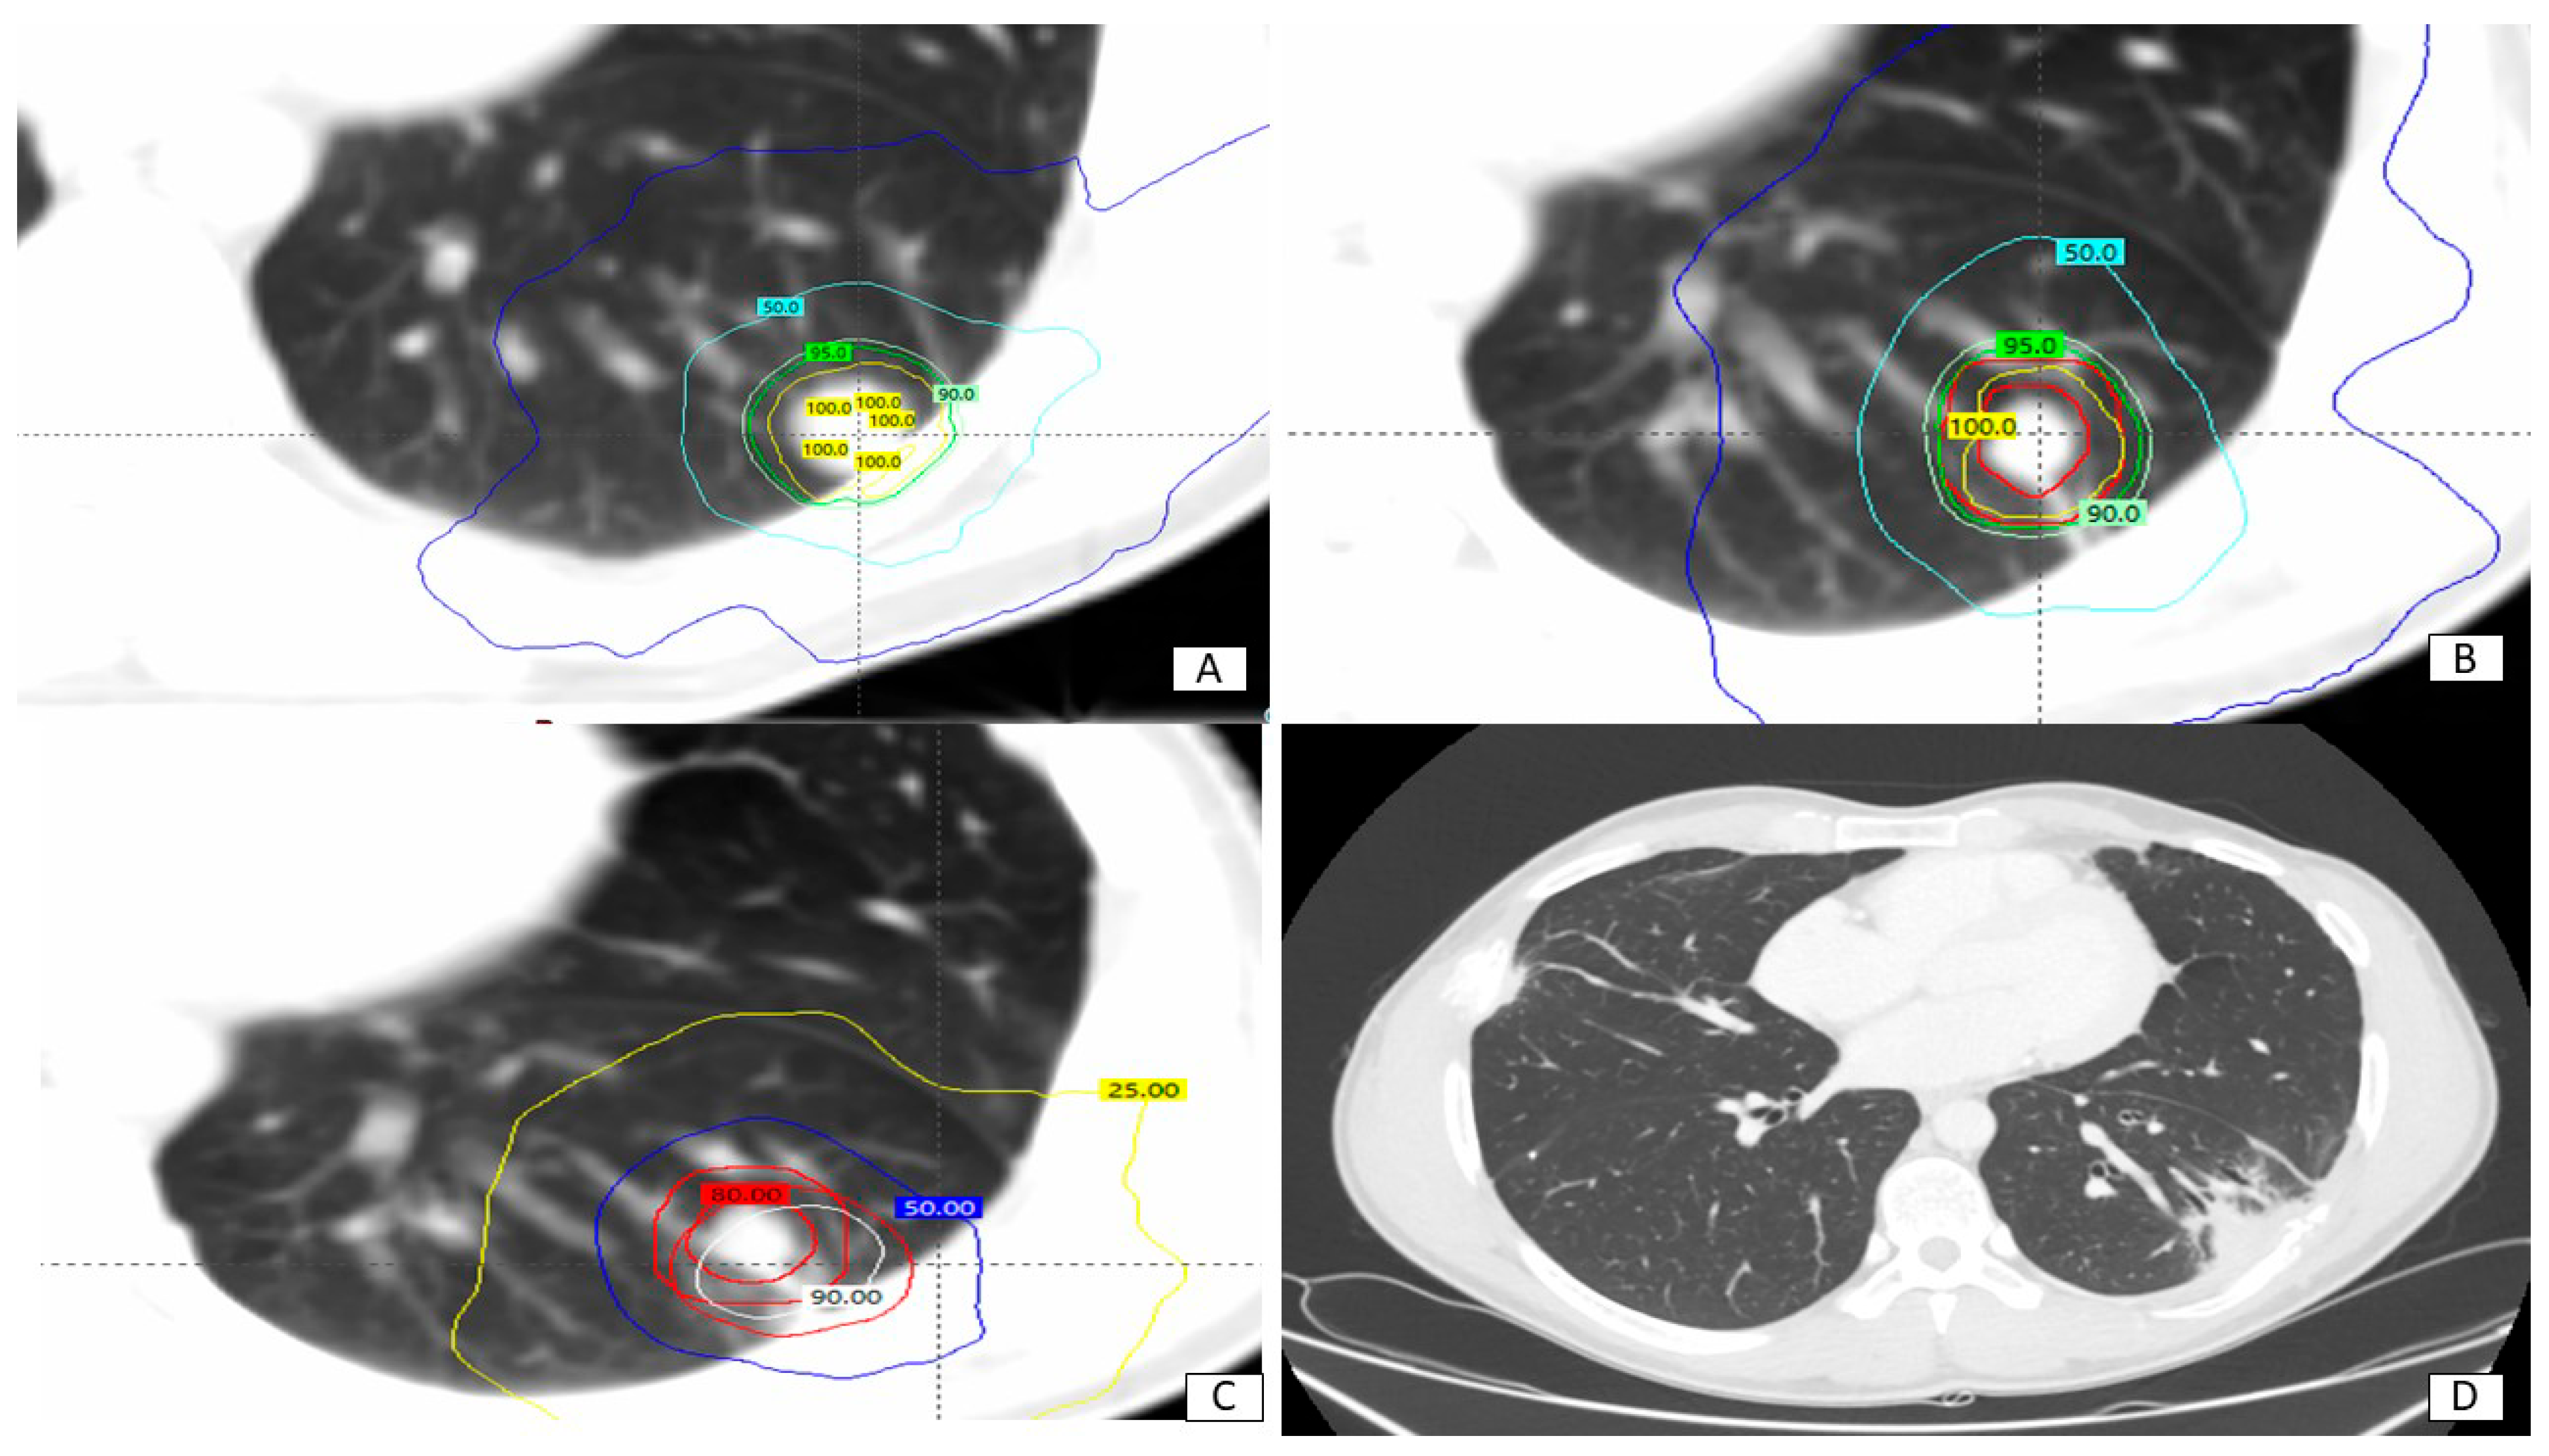

| SBRT TOTAL DOSE IN 5 FRACTIONS 30 Gy 40 Gy 50 Gy | 5 5 5 | 33% 33% 33% |